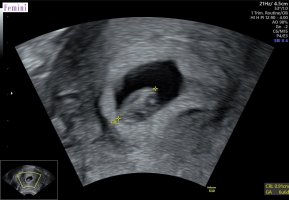

et spm ; noen som på ultralyd har hatt et ekstra hulrom i livmor? Altså som om det skulle vært en til der, men ingen tegn til et foster ? Jeg hadde det, så hun lette litt ekstra etter en til, men sa at hun ikke kunne si at det hadde vært en til der, og at jeg definitivt kun hadde en inni der nå. Jeg har ikke blødd , så det hele var litt merkelig? Aldri opplevd før![]()

fine hjerteslag på 162